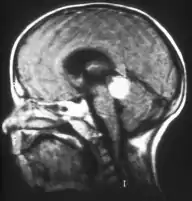

Inherited forms of retinoblastomas are more likely to be bilateral. In addition, inherited uni- or bilateral retinoblastomas may be associated with pineoblastoma and other malignant midline supratentorial primitive neuroectodermal tumors (PNETs) with a dismal outcome; retinoblastoma concurrent with a PNET is known as trilateral retinoblastoma.[15] A 2014 meta-analysis showed that 5-year survival of trilateral retinoblastoma increased from 6% before 1995 to 57% by 2014, attributed to early detection and improved chemotherapy.[16]

Aspect of trilateral retinoblastoma on MRI

Traditional ultrasound B scan can detect calcifications in the tumour while high-frequency ultrasound B scan is able to provide higher resolution than the traditional ultrasound and determine the proximity of the tumour with front portion of the eye. MRI scan can detect high-risk features such as optic nerve invasion; choroidal invasion, scleral invasion, and intracranial invasion. CT scan is generally avoided because radiation can stimulate the formation of more eye tumours in those with RB1 genetic mutation.[35]